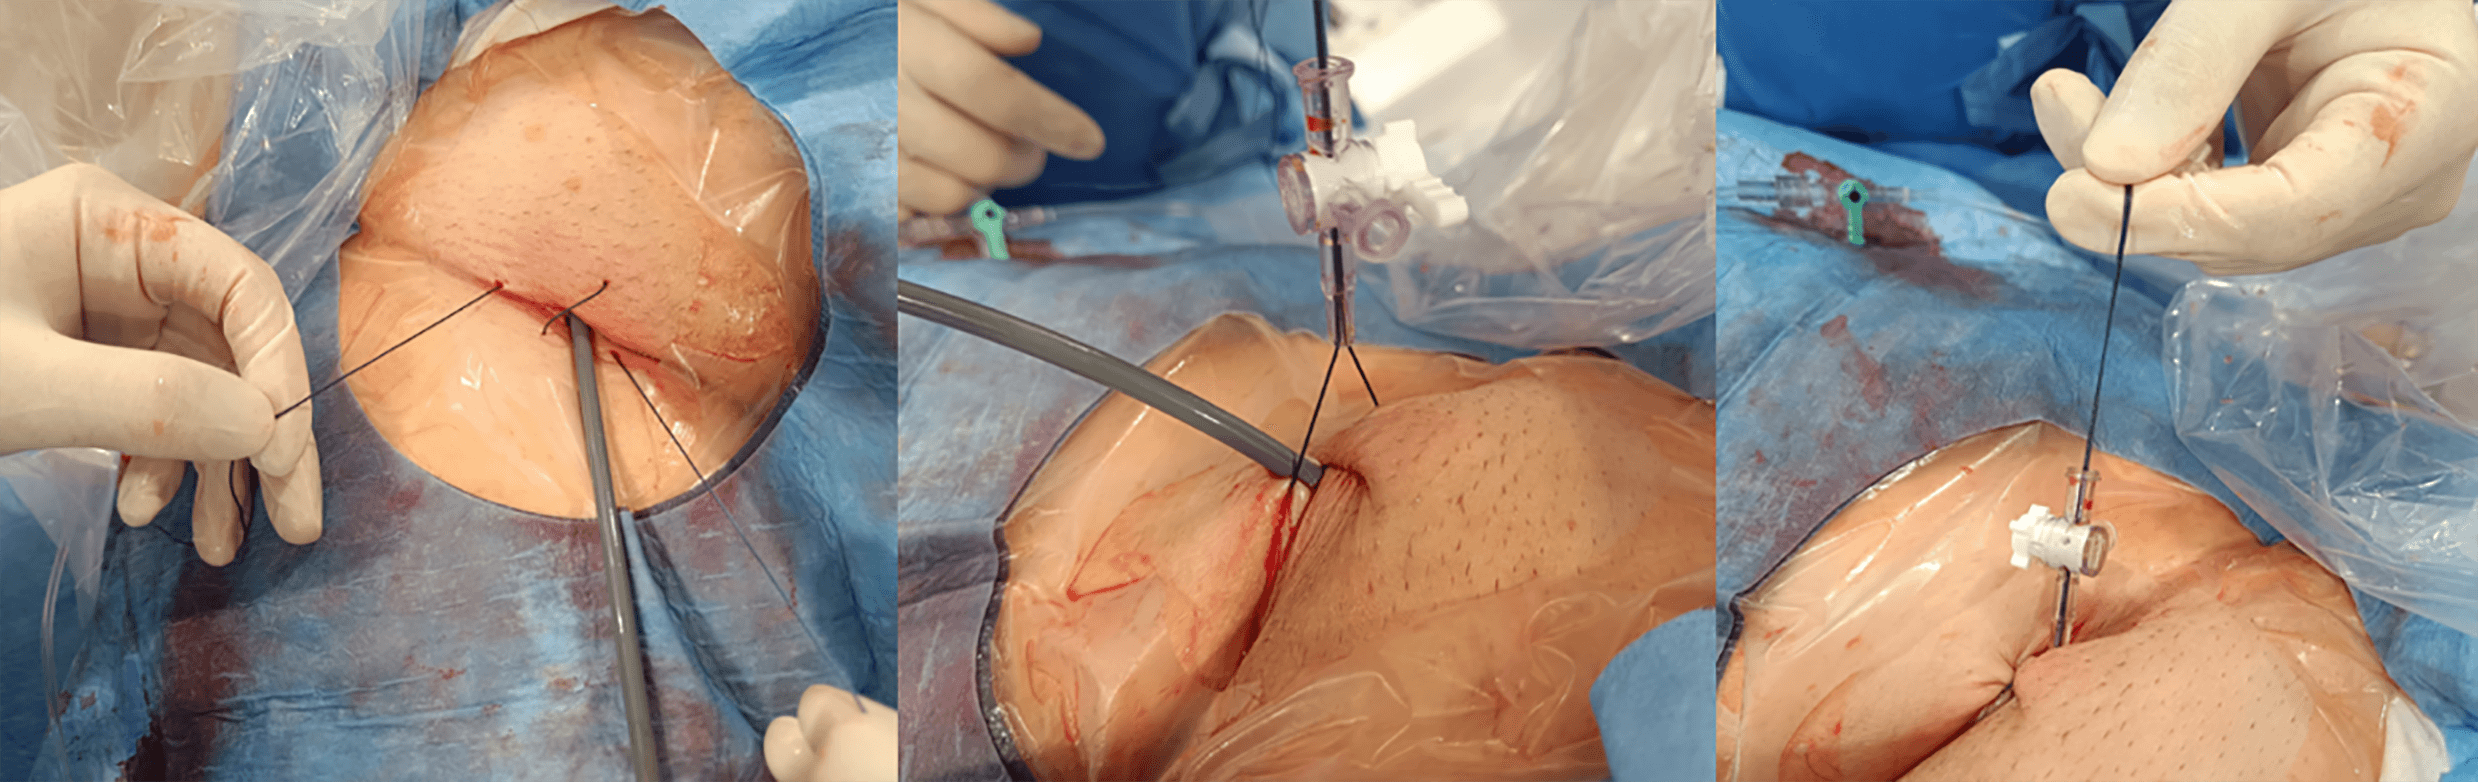

For femoral access site management, we routinely use a figure-of-eight suture technique. The sutures are passed through the side port of the introducer (previously cut), tension is applied to achieve hemostasis, and the closure is secured by locking the stopcock (Fig. 17).

Fig. 17.